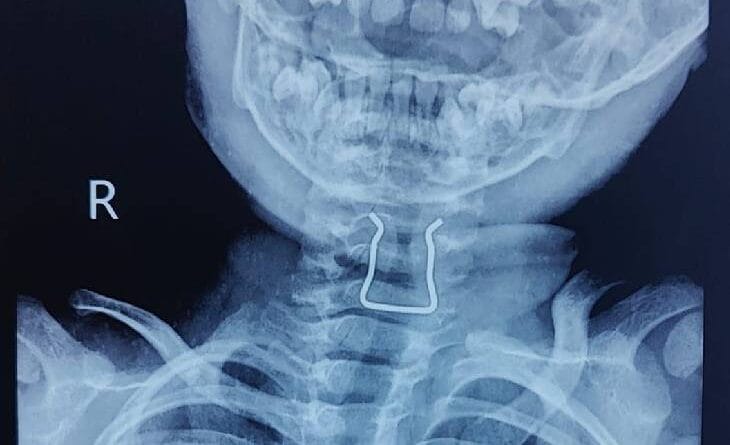

जबलपुर में दो साल के मासूम ने निगली पिन, गले में फंसी; डॉक्टरों ने 30 मिनट ऑपरेशन कर निकाली

जबलपुर (वाजिद खान)। जबलपुर में दो साल के मासूम ने खेल-खेल में खिलौने की पिन निगल ली। एक सेंटीमीटर लंबी